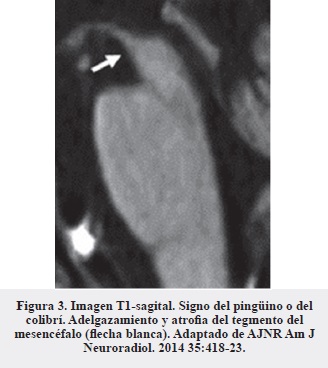

En el diagnóstico diferencial con degeneración corticobasal es importante buscar la atrofia cortical marcada unilateral característica de esta entidad (Figura 6) (17, 19) y de las afasias primarias progresivas y ausentes en la PSP, en las que la atrofia es más generalizada (17).